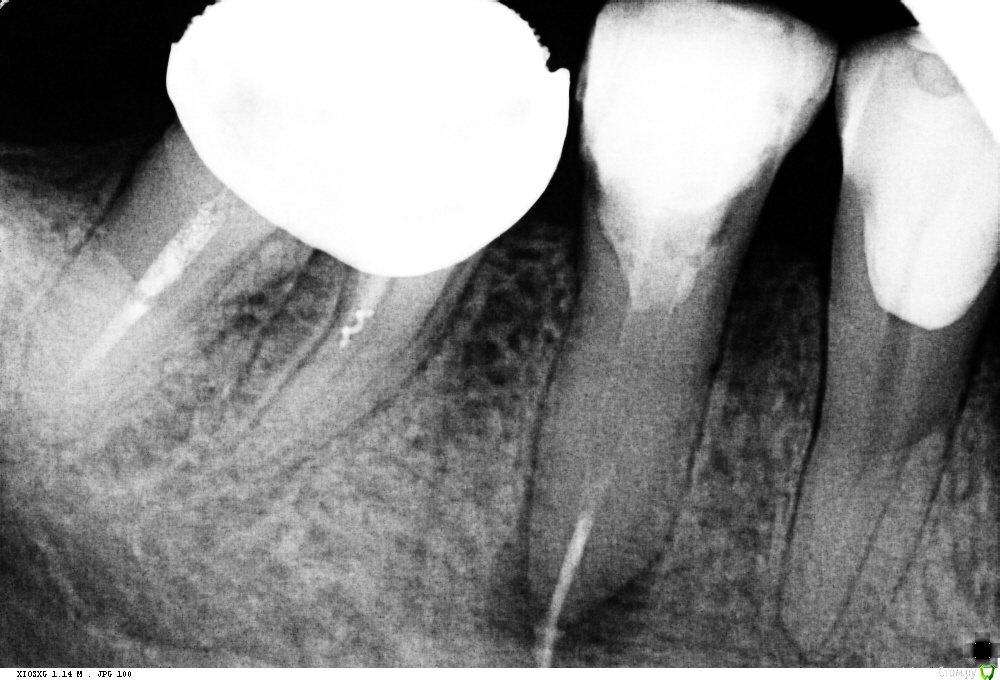

St. Опубликовано 13 октября, 2016 Поделиться Опубликовано 13 октября, 2016 История такова. Год назад зуб был с большой пломбой, но без периапикальных изменений на панораме. Никак себя не проявлял. 2-3 мес.назад со слов стал ныть, потом боль стала сильнее и проходила только от холодной воды. Тут вроде как ясно, классический гнойный пульпит. Болел ли тогда при накусывании пациент не помнит. Пошел к врачу, за 1 прием полечили каналы. На след.раз поставили постоянную пломбу. Через несколько дней пломба выпала. Поставили новую на стекловолокне. Боль вроде прошла.Сейчас появились боли при накусывании. Учитывая что до этого лечение было в гос и как минимум без коффа, решила перебрать. Не знаю, правильно ли?Но уже как есть. Достала СВЩ не очень удачно - истончила дист. стенку. Распломбировала. То что за апексом - скорее всего силлер( н-файлом не удится ничего). Получили экссудат. Сейчас на гидроокиси. У кого какие мысли как быть дальше? Собственно как лучше запломбировать и чем восстановить зуб после. Ссылка на комментарий

St. Опубликовано 13 октября, 2016 Автор Поделиться Опубликовано 13 октября, 2016 По первоначальному снимку вы бы ревизию делали? или сразу к хирургу? Ссылка на комментарий

Ker Опубликовано 14 октября, 2016 Поделиться Опубликовано 14 октября, 2016 На 6 гранулёма тоже растет и здравствует, а с 5 всё плохо...Доставать стекловолокно это то еще испытание. Ссылка на комментарий